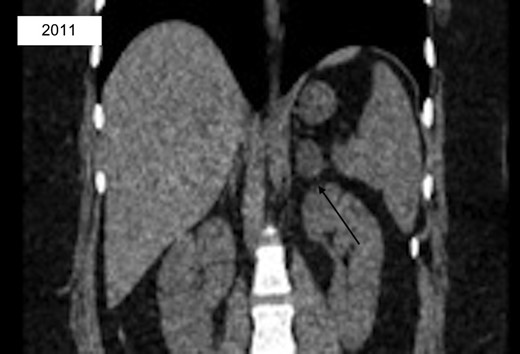

A 27-year-old Caucasian female with a past medical history significant for untreated hypertension, irritable bowel syndrome, hidradenitis, and ovarian cysts presented to the emergency department for evaluation of a three-day history of left flank pain. She had a prior CT scan seven years prior at which time a 2.7 × 2.1 cm left adrenal lesion, consistent with an adenoma, was found (Fig. 1). At recent presentation, non-contrast CT scan of the abdomen and pelvis was performed, demonstrating a 5.6 × 3.7 × 4.0 cm mass contiguous with the left adrenal gland and splenic artery (Fig. 2). She was ultimately discharged home with recommendation for further outpatient workup. Subsequent CT of the abdomen and pelvis with IV contrast revealed a 5.0 × 6.2 cm left adrenal mass. Portal phase density was 67 HU with washout seen at 15 minutes with HU of 42. MRI of the abdomen with adrenal protocol was then performed, depicting a 4.7 × 5.9 cm enhancing left adrenal mass with a differential diagnosis of pheochromocytoma, adrenal carcinoma, and metastatic disease. Biochemical workup was unremarkable aside from an elevated total/free testosterone of 124 ng/dl and 17.2 pg/ml. However, a diagnosis of polycystic ovarian syndrome was discussed with her in the past. The patient was then seen in the surgical oncology clinic at which time she complained of persistent left flank pain with no abnormal findings on physical examination. Surgical resection was recommended and patient underwent a robotic assisted laparoscopic left adrenalectomy. She had an uncomplicated post-operative course and was discharged home the following day. Surgical pathology revealed a high grade ACC measuring 8.4 cm in greatest dimension. There was invasion into the adrenal capsule and presence of small vessel lymphovascular invasion. Surgical margins were uninvolved with distance to closest radial margin of one mm. Immunostain showed significantly elevated Ki-67 labeling index up to 30% in focal areas of the tumor. The tumor also showed focal mitotic activity ranging from 0-4 mitoses/HPF, resulting in a diagnosis of high grade ACC. This case was discussed at a multidisciplinary meeting and adjuvant treatment was recommended. She then received external beam radiation to the left adrenal bed with a total dose of 5040 cGy at 180 cGy/F. She established care with medical oncology and was started on Mitotane with a goal dose of 6000 mg/day and goal level of 14-20 mcg/mL.

CT abd/pelvis with incidental finding of left 2.7 × 2.1 cm low-density adrenal lesion consistent with adenoma.